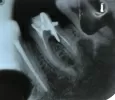

На снимке похоже, что арматуринка перфорировала корень. И видно воспаление под дном зуба между корней (в зоне предполагаемой перфорации). Возможно ли запечатать такое прободение, нужны ли дополнительные снимки, 3D, КТ? Или зуб уже точно потерян?

• По данному рентгеновскому снимку зуб подлежит удалению, так как есть большой очаг воспаления в области бифуркации корней зуба, перфорация корня вкладкой, выведен пломбировочный материал за верхушку корня зуба. После удаления, образовавшийся дефект следует заместить имплантатом или мостовидным протезом.